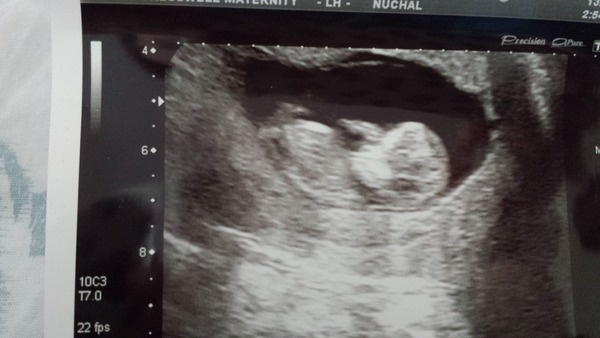

All well at the scan yesterday - I'll post a scan pic in a bit. Hospital didn't comment on probability based on nuchal fold as they do the combined assessment with bloods too, so I'll hear by letter. But measurement was 1.5mm which as I understand it is nowt to worry about.

PallasCat · 20/10/2015 16:22

PallasKitten at 13+1. Nub theorists and skull theorists, I'd love to hear your guesses!

Boy skull I would hazard a guess at!

I'd say boy too!